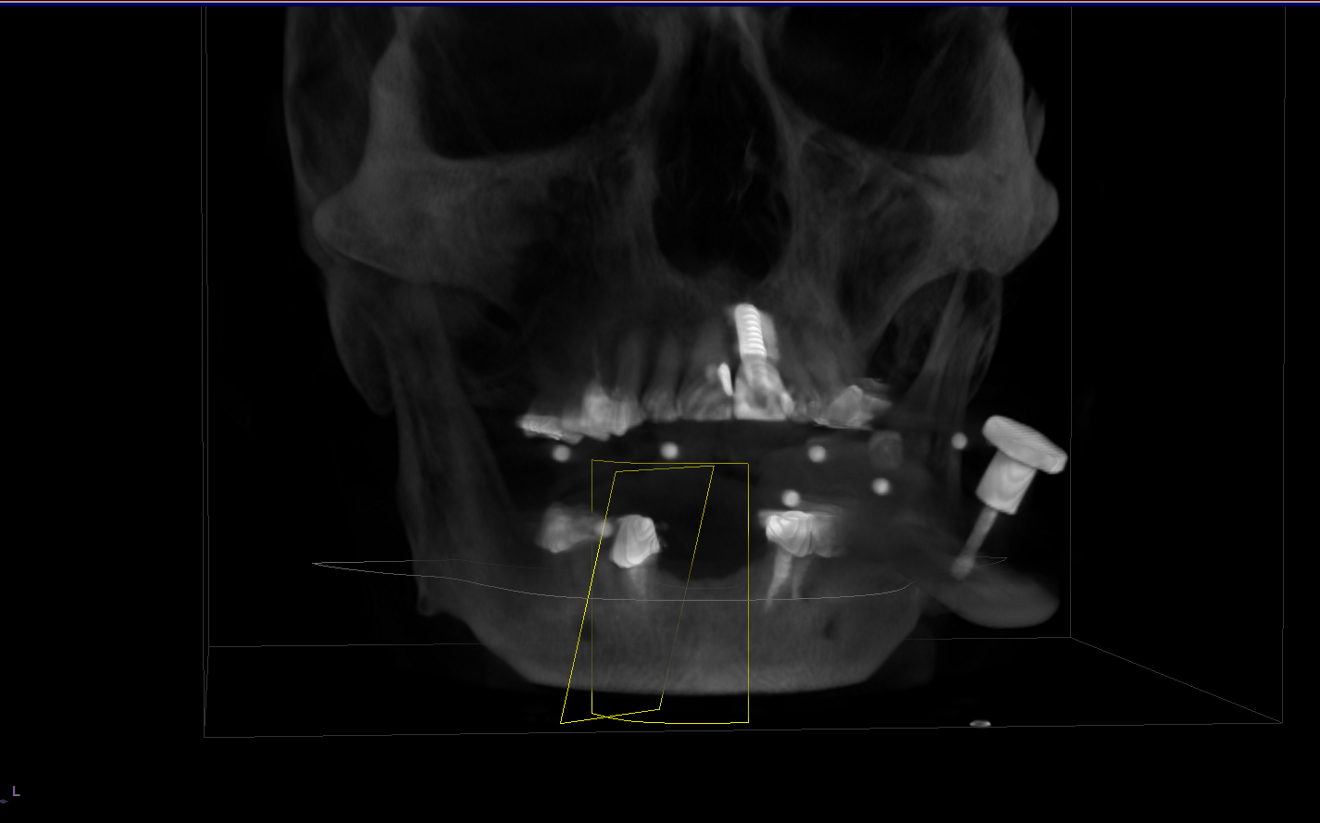

Preoperative planning was performed using CBCT (Axeos and Galileos, Dentsply Sirona; Fig. 3) and YomiPlan planning software (Neocis) to select and parallel all the implants (Fig. 4). Preoperative maxillary, mandibular and bite scans were taken with CEREC Primescan (Dentsply Sirona) and sent to the laboratory for a temporary mock-up (Fig. 5). This allowed the laboratory technician to pre-plan a temporary restoration and discuss implant positions and final prosthetic solutions.

Fig. 3: 3D implant planning with the Galileos software.

Fig. 4: Implant planning and parallelisation with YomiPlan.